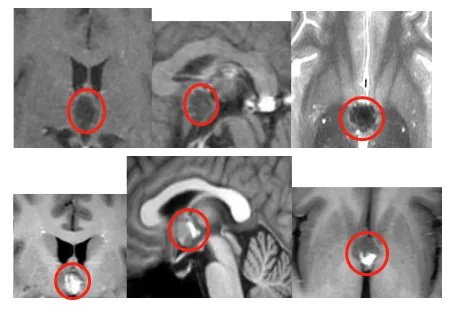

▼浩然第一次检查影像MRI

核磁检查的结果出来后,医生告诉浩然,考虑第三脑室病变,疑似海绵状血管瘤,约14×13×10mm大小。